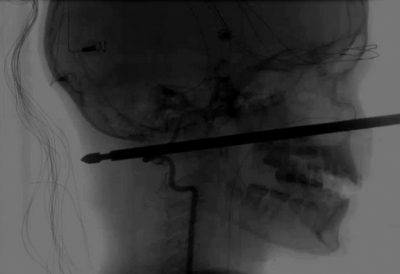

Menino que teve cabeça empalada por espeto de churrasco diz ter sido salvo por 'Pantera Negra' (Foto: Divulgação)

Um garotinho de 11 anos que teve a cabeça empalada por um espeto de churrasco diz ter sido salvo pelo filme do herói Pantera Negra. O acidente envolvendo o jovem Xavier Cunningham ocorreu em setembro do ano passado, mas só agora ele foi liberado do hospital em que esteve internado e em recuperação. Em seu relato sobre o ocorrido, Xavier contou que estava na casa da árvore de sua família quando foi atacado por vespas. Ele tentou fugir dos insetos, caiu de uma escada de 1,5 metro em cima do espeto de churrasco. O objeto de metal entrou logo abaixo do olho esquerdo da criança e saiu na nuca dele.

Em entrevista ao site da revista People, Xavier disse que o final do filme ‘Pantera Negra’ foi essencial para sua sobrevivência. Ele disse não ter removido a barra de metal de seu rosto após o acidente pois se lembrou do destino fatídico do vilão Erik Kilmonger, que morre após remover uma lança em seu peito. “Eu assisti ‘Pantera Negra. No final, ele tira a lança e morre, então não tirei”, explicou o garoto.